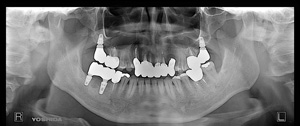

@@R.S‚³‚ñ@56Î —«  ‘åŠw‹³Žö @Žèp“ú@‚Q‚O‚O‚W”N ‚QŒŽ ‚X“úi“yj@㉺Š{  ƒm[ƒxƒ‹ƒKƒCƒhŽg—p@Ö¬“à’ÁÖ@•¹—p@@@

@@@@@ãŠ{  All on ‚U@‘¦Žž‰Ád@@

@@@@@@@@@@@@@ Rpl Tapered Rp  ‚P‚O mm(‚U–{)

@@@@@‰ºŠ{¶‰E@‘¦Žž‰Ád@ ‚R Unit Bridge@

@@@@@@@@@@@ @Rpl Tapered Rp  ‚P‚O mm(‚S–{)@@–ƒWƒ‹ƒRƒjƒAƒNƒ‰ƒEƒ“‚ÅÅI•â’Ô